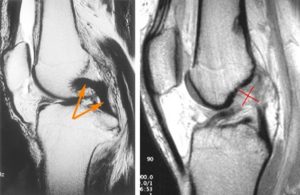

- МРТ. Также весьма эффективным методом является магнитно-резонансная томография. При её проведении используются электромагнитные волны, которые позволяют визуализировать не только плотные, но и мягкие материи. Благодаря этому можно отследить разновидность травмы.

Магнитно-резонансная томография позволяет увидеть все повреждения сустава, в том числе крестообразных связок, в 3d проекции.

- МРТ. Магнитно-резонансная томография является наиболее точной методикой подтверждения диагноза в отношении дегенерации связок колена с вероятностью до 95%;